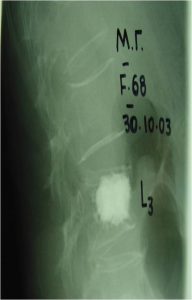

δ. Γενικότερα, η τελειοποίηση των ακτινολογικών μηχανημάτων, δίνει πολύ καλύτερη απεικόνιση των ελεγχόμενων περιοχών της Σπονδυλικής Στήλης, με συνέπεια η τοποθέτηση των υλικών σπονδυλοδεσίας να γίνεται με μεγαλύτερη ακρίβεια. Ορισμένες δε επεμβάσεις όπως είναι η σπονδυλοπλαστική – κυφοπλαστική, μπορούν να πραγματοποιούνται με μεγαλύτερη ασφάλεια λόγω σαφέστερης απεικόνισης των ανατομικών στοιχείων.

Εικόνα 3 (α,β,γ) : Προεγχειρητική Μαγνητική Τομογραφία, πλαγία λήψη ακολουθία Τ2, καταστροφή του οσφυϊκού σπονδύλου συνεπεία μετάστασης από το μυελό. Δια κυφοπλαστικής (β,γ) πραγματοποιήθηκε αποκατάσταση του σπονδυλικού σώματος.